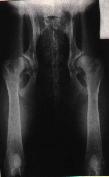

ŠPATNĚ PROVEDENÝ RTG SNÍMEK!!

Projekce není symetrická - stehenní kosti a podélná

osa těla nejsou rovnoběžné. |

Dále by se měla věnovat velká pozornost projekčně

dokonalému snímku. Jakékoli nevyhovující kvalita snímku může poté opět

negativně ovlivnit konečné hodnocení snímku, zejména v případě

hraničních stupňů dysplazie.